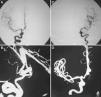

The present report describes the case of a patient with a history of pituitary macroadenoma, who had undergone a partial transsphenoidal resection ten years earlier. Admission to our service occurred after a sudden headache followed by mental confusion. A cranial computed tomography showed subarachnoid haemorrhage and expansive suprasellar lesion. Cerebral angiography showed a saccular aneurysm of the anterior communicating complex. The patient underwent a surgical procedure for microsurgical clipping of the aneurysm and partial resection of the pituitary tumour. We have also included a brief review of the literature on this subject.

El presente informe describe el caso de una paciente con antecedentes de macroadenoma hipofisario, que fue sometido a una resección transesfenoidal parcial diez años antes. La entrada a nuestro servicio se produjo después de que un dolor de cabeza repentino seguido por la confusión mental. Una tomografía computarizada craneal mostró hemorragia subaracnoidea y lesión supraselar expansiva. La angiografía cerebral mostró un aneurisma sacular del complejo comunicante anterior. El paciente se sometió a un procedimiento quirúrgico para clipaje de aneurisma y la resección parcial del tumor pituitario. También hemos incluido una breve revisión de la literatura sobre este tema.